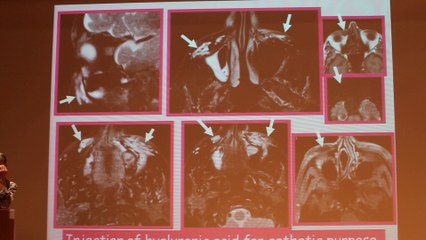

Extra Axial Lesions - Françoise Héran - Wednesday 29th January - Part 1